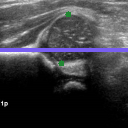

The correlation statistics are already high enough for our automated tool to be widely adopted for infant hip screening. It is nevertheless essential to acknowledge that the false negative cases are not to be taken lightly. In Fig. 5 we illustrate the subtle differences between individual scans from the four possible categories. Fig. 5(a) shows a true positive example, with AFHC=39.6%, an error of less than 0.04% to SGT. It is worth noting that, for 128×128128128128{\times}128 pixel images, a disagreement of one pixel represents a percentage difference of 0.78% across the whole image, and approximately 1.5% across the span of the femoral head structure. Fig. 5(b) shows a true negative example, with AFHC=62.4%, an error of less than 0.39% to SGT. Fig. 5(c) shows the most severe of the false positives. The algorithm under-segments the lowermost component of the femoral head, with AFHC=43.3%, compared to a SGT FHC of 50.4%. Fig. 5(d) shows the most severe of the false negatives. The algorithm over segments the lowermost component of the femoral head and also slightly over segments the ilium on its upper edge by including a small bump of cartilage. There is only little of the horizontal length of the ilium visible in the image; this affects the ilium edge disproportionately, and thus the algorithm calculates AFHC=60.1%, whereas the SGT FHC is 49.9% (a figure which would have caused a clinician to keep the patient under observation).

Refer to caption

(a)

Fig. 5: Qualitative analysis of AFHC% and its corresponding diagnostic outcomes: (a) True positive. (b) True negative. (c) False positive. (d) False negative diagnosis.